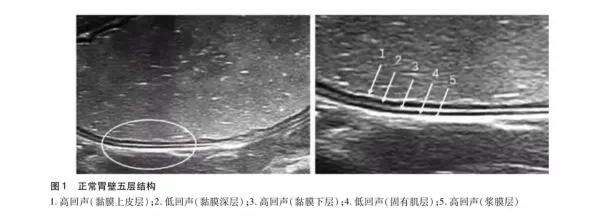

于长路主任说 , 胃肠充盈超声造影检查 , 是通过一种造影剂充盈胃肠腔的检查 , 该类造影剂充盈胃肠腔后在声像图上显示类似于实质性组织的回声 , 消除了胃腔内的气体及黏液干扰 , 和胃肠壁及肝、胆、脾、胰之间产生明显的对比效应 , 清晰地显示胃肠壁的层次结构 , 从而使胃肠内腔产生良好的声学造影效果 。

(正常胃壁声像图)